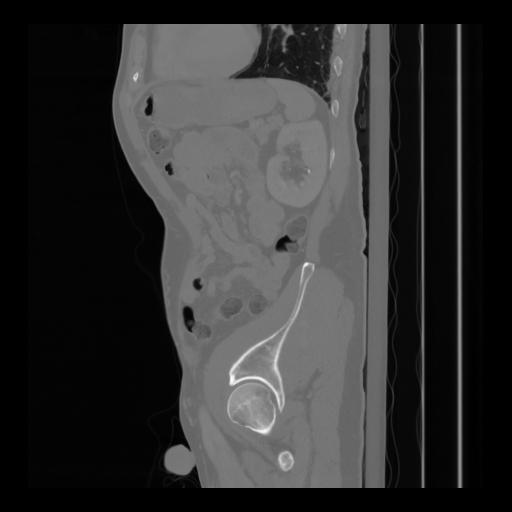

36 CUERPO,CE,Sagittal,3.000,CUERPO,Sagittal,